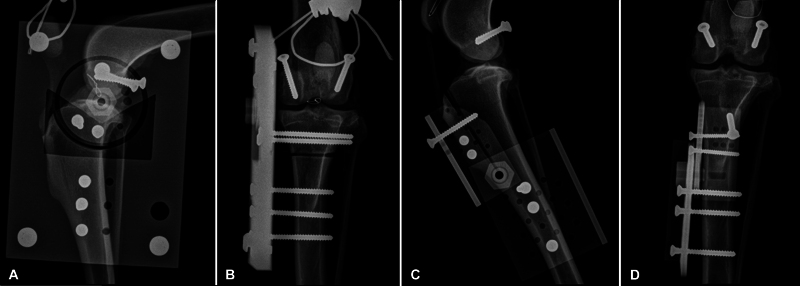

Objectives:  The aim of the study was to investigate the contact mechanics and kinematic changes in the stifle in different standing angles.

Study design:  We performed a biomechanical ex vivo study using pairs of canine cadaver hindlimbs. Motion sensors were fixed to the tibia and the femur for kinematic data acquisition. Pressure mapping sensors were placed between the femur and both menisci. Thirty percent bodyweight was applied to the limbs with the stifle in 125, 135, or 145 degrees of extension.

Results:  Stifle flexion angle influences femoromeniscal contact mechanics significantly. The load on both menisci was significantly higher for 125 and 135 degrees in comparison to 145 degrees. Additionally, the center of force was located significantly more caudal when comparing 125 to 145 degrees in the medial meniscus as well as in both menisci combined.

Conclusion:  The angle of knee flexion significantly impacts the contact mechanics between the femur and the meniscus. As the knee flexes, the load on both menisci increases.